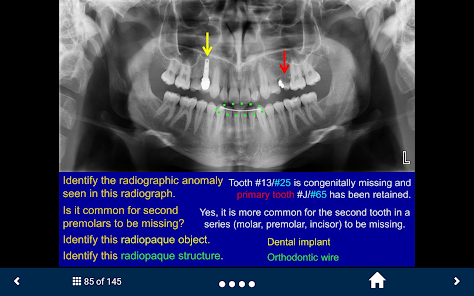

Oral Radiology - SecondLook is an educational self-assessment tool developed by the University of Michigan. The application facilitates learning by presenting a series of high-quality radiographic images, including intraoral, panoramic, and CBCT scans. It utilizes a guided question-and-answer format to help users test their ability to identify anatomical structures, technical errors, and maxillofacial pathologies. This interactive mechanism supports knowledge reinforcement in key areas of oral radiology, from basic anatomy to complex disease presentation.

This application is designed as an educational support resource for dental and health sciences students. Its primary scope is to provide a self-assessment platform for reviewing radiographic images and reinforcing knowledge of oral pathology and anatomy. The tool is intended for study purposes only and is not a substitute for clinical instruction or a diagnostic aid.